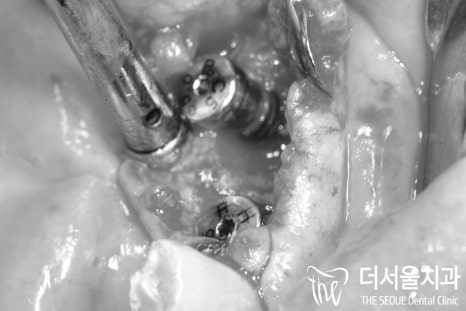

【 수술 진행 】

이렇게, 컴퓨터 진단 내용에 따라서

예상 했던 위치에 그대로 Implant fixture 를

심어드리게 되었습니다.

본래, 어금니가 있어야 될 자리를 대체하는

포지션이기 때문에 뼈 속 깊숙히

심어드린 것을 보실 수 있습니다.

뼈이식도 함께 동반하여

모자란 치조골의 양을 빼곡히 채워줬죠.